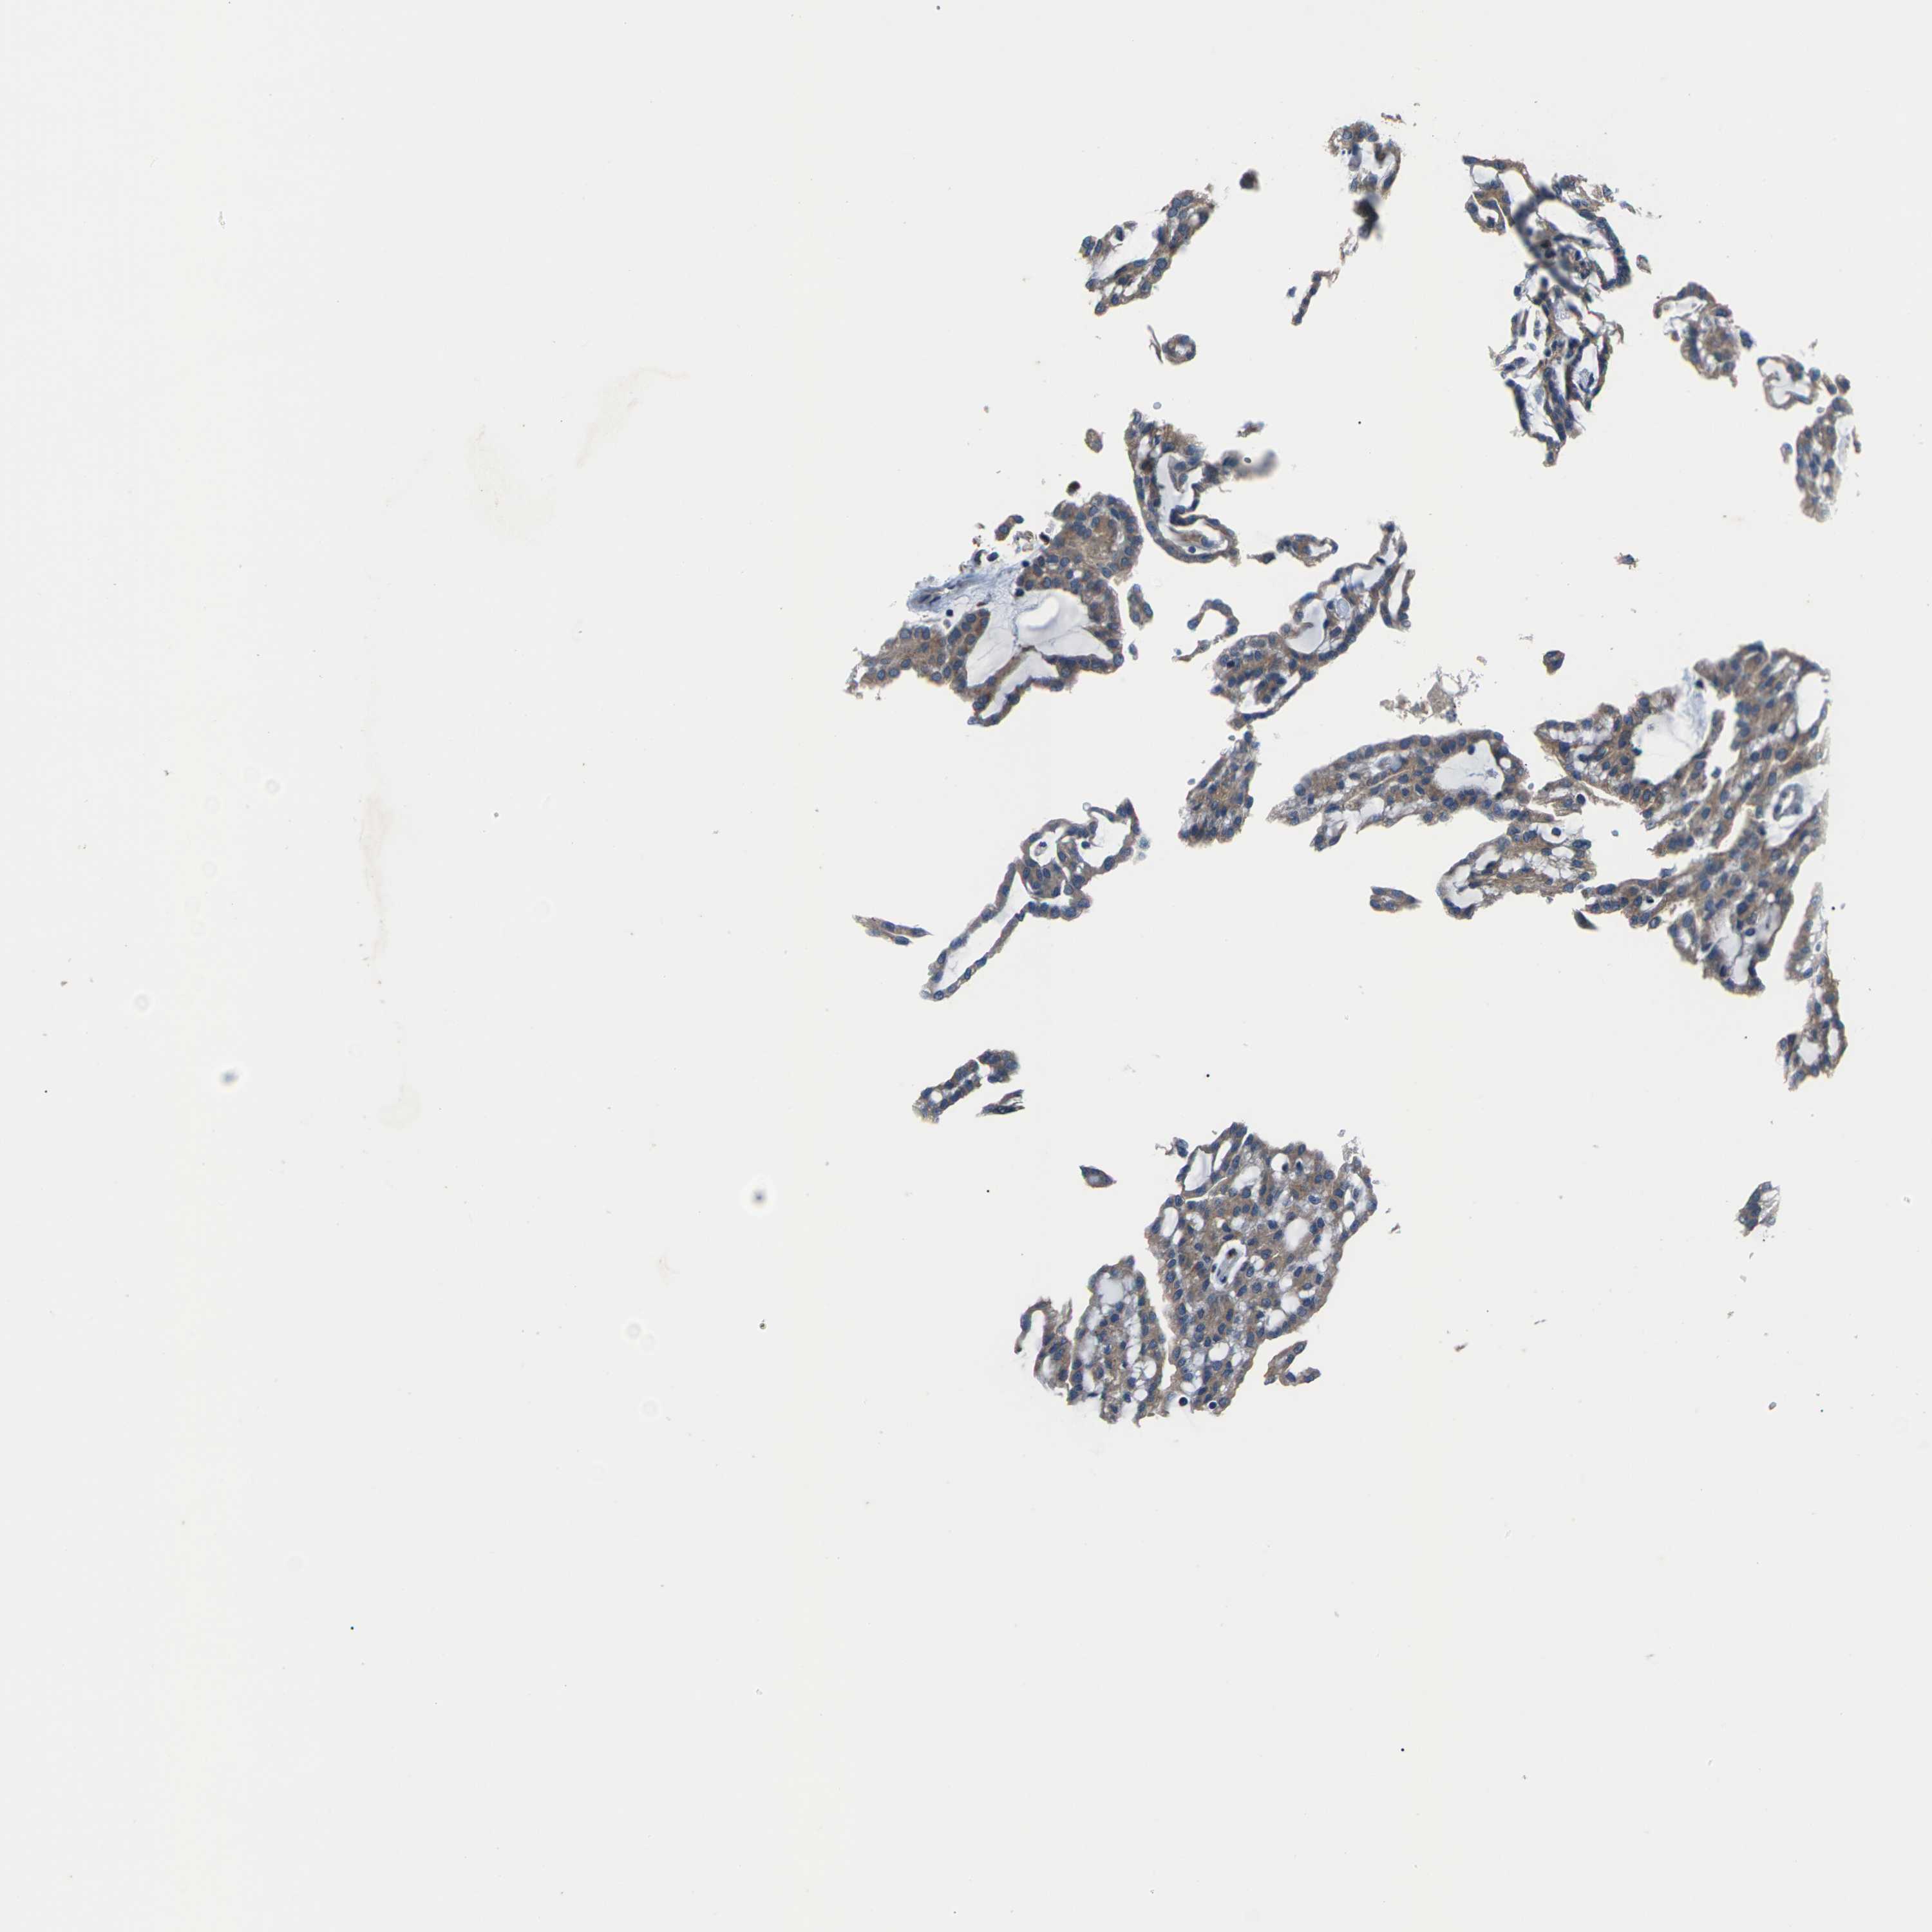

KIDNEY RENAL CLEAR CELL CARCINOMA (VALIDATION) - Interactive survival scatter ploti

The Survival Scatter plot shows the clinical status (i.e. dead or alive) for all individuals in the patient cohort, based on the same data that underlies the corresponding Kaplan-Meier plots. Patients that are alive at last time for follow-up are shown in blue and patients who have died during the study are shown in red.

The x-axis shows the expression levels (FPKM) of the investigated gene in the tumor tissue at the time of diagnosis. The y-axis shows the follow-up time after diagnosis (years). Both axes are complimented with kernel density curves demonstrating the data density over the axes. The top density plot shows the expression levels (FPKM) distribution among dead (red) and alive patients (blue). The right density plot shows the data density of the survived years of dead patients with high and low expression levels respectively, stratified using the cutoff indicated by the vertical dashed line through the Survival Scatter plot. This cutoff is automatically defined based on the FPKM cutoff that minimizes the p-score. The cutoff can be changed by dragging the vertical line or by entering a cutoff value in the square labeled "Current cut-off".

Under the Survival Scatter plot the p-score landscape (black curve; left axis) is shown together with dead median separation (red curve; right axis). Dead median separation is the difference in median mRNA expression between patients who have died with high and low expression, respectively. It is calculated as follows: median FPKM expression of dead patients with high expression - median FPKM expression of dead patients with low expression. This is intended to aid the user in visually exploring custom cutoffs and the associated p-scores and dead median separation.

Individual patient data is displayed and can be filtered by clicking on one or more of the category buttons on the top of the page. Categories describing expression level and patient information include: high, low, alive, dead, female, male and tumor stages. The scale of the x-axis can be toggled between linear and log-scale by clicking on the "x log" button. Mouse-over function shows TCGA ID, patient information and mRNA expression (FPKM) for each patient.

& Survival analysisi

Kaplan-Meier plots summarize results from analysis of correlation between mRNA expression level and patient survival. Patients were divided based on level of expression into one of the two groups "low" (under cut off) or "high" (over cut off). X-axis shows time for survival (years) and y-axis shows the probability of survival, where 1.0 corresponds to 100 percent.

GABRP is not prognostic in Kidney Renal Clear Cell Carcinoma (validation)

: 9.26

Average pTPM 10.1

Number of samples 100